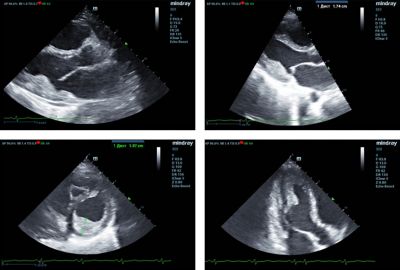

Two-dimensional transthoracic echocardiography was performed on a Mindray M9 ultrasound machine using monocrystal sector SP5-1s transducer. The examination revealed a 20 mm thick hyperechoic mass in the left ventricular (LV) cavity, closely associated with the inferior and inferolateral segments of the LV myocardium. This mass involved the posteromedial papillary muscle, posterior mitral valve leaflet and caused moderate mitral regurgitation. (Figure 1,2).

Fig. 1 - Hyperechoic mass in the LV cavity involving myocardium, papillary muscle and posterior mitral valve leaflet.

A slight dilatation of both atria, moderate tricuspid regurgitation, overload, and decreased contractility of the right ventricle (TAPSE = 12), moderate pulmonary hypertension (Figure 3), and restrictive transmitral blood flow (Figure 4) were also detected. LV ejection fraction (EF) was preserved (65%).

Fig. 3 - The echocardiography patterns of pulmonary hypertension.

Fig. 4 - The restrictive pattern of trans-mitral flow.

Speckle tracking was performed to assess LV contractility. According to TTQA results global longitudinal strain (GLS), Global longitudinal Strain Rate (GLSR), Global Radial strain (GRS) were decreased. (Figure 5)

Fig. 5 - TT QA revealed reduced LV GLS (-) - 13%, GLSSR – 0,87 1/s, GRS - 28%.